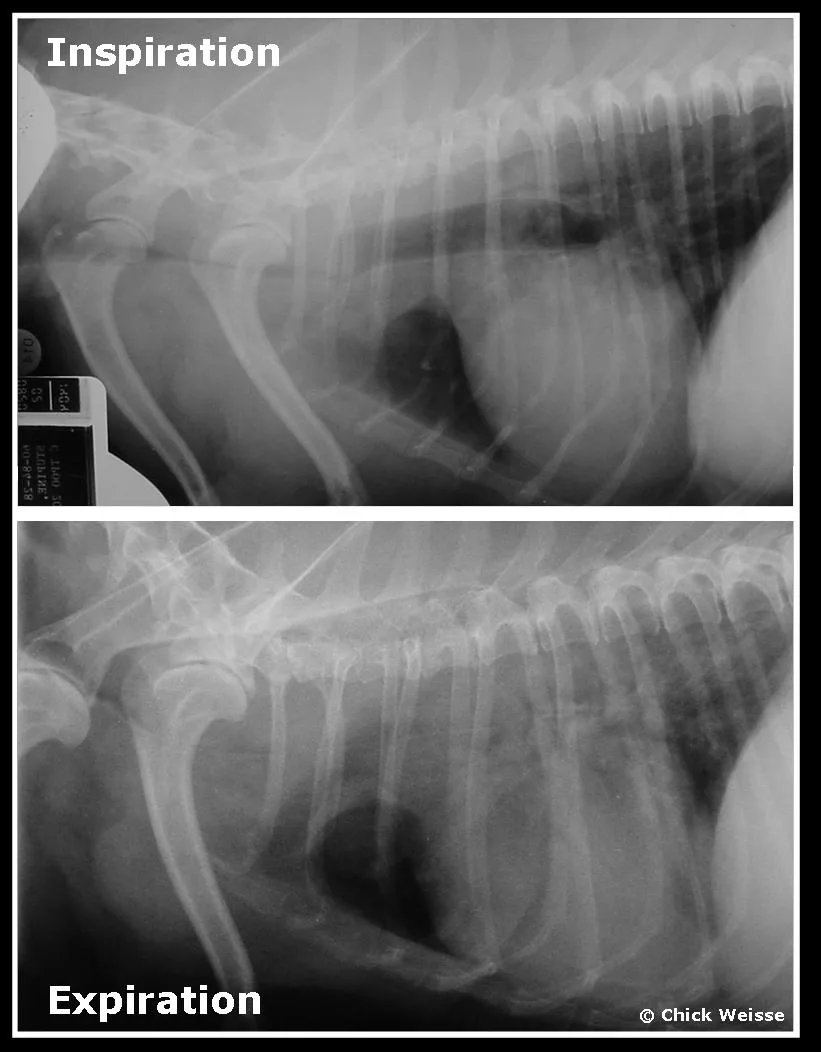

Diagnosis. Accurate diagnosis of the location of the collapse is important before choosing which technique to perform or recommend. Routine radiography can be useful for diagnosis of concurrent conditions and the presence of tracheal collapse, but more dynamic studies are necessary to fully appreciate the extent of the collapse. During inspiration, the subatmospheric airway pressures generated in the cervical trachea lead to collapse in that location; during expiration, increased intrathoracic pressures lead to collapse of the intrathoracic trachea. Individual static radiographs may fail to document the full extent of the collapse as shown above, which is the same dog during two different phases of respiration (cervical tracheal collapse during inspiration and intrathoracic tracheal collapse during expiration).